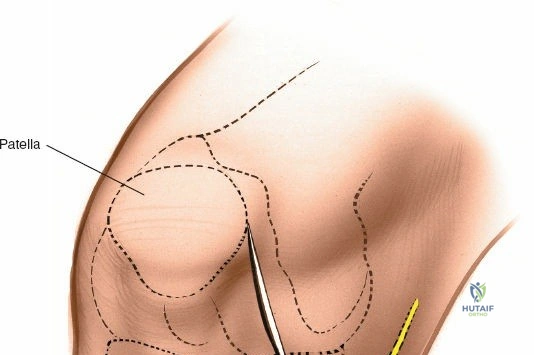

Landmarks and Incision:

- Landmarks: Palpate the medial joint line, medial epicondyle of the femur, and medial tibial plateau. The saphenous vein and nerve courses superficial and posterior to the medial femoral condyle, requiring careful attention.

Exposure of the Meniscus:

- Retractors are carefully placed to expose the medial tibiofemoral compartment. Self-retaining retractors may be used, but care must be taken to protect the articular cartilage.

- To improve visualization, the knee is brought into hyperflexion (as per seed content, "beyond a right angle"). This maneuver, combined with external rotation of the tibia and a valgus stress applied to the knee, widens the medial compartment. This allows for improved access to the posterior horn of the medial meniscus.

- Inspection: Thoroughly inspect the medial meniscus to identify the tear pattern and assess its stability using a blunt probe.